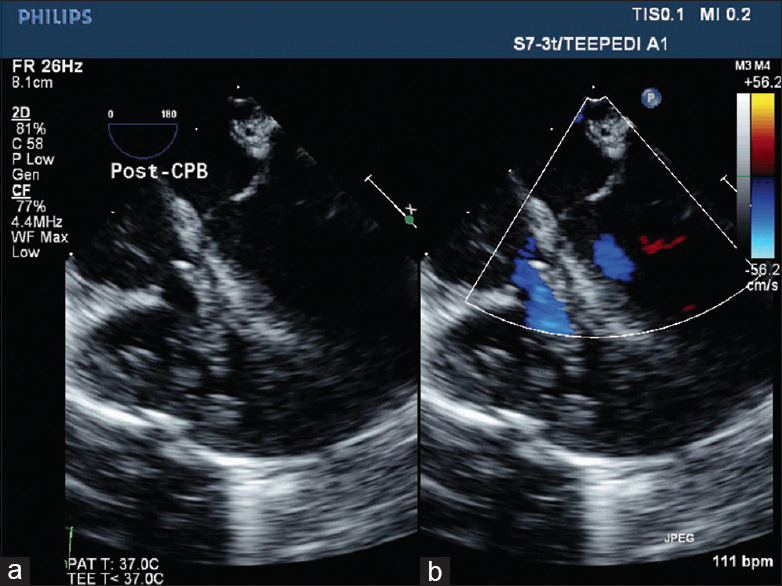

Association of Ebstein's anomaly of tricuspid valve (TV) with tetralogy of Fallot (TOF) is extremely rare. Their coexistence is unique as they modify each other's physiology. We report a case of a girl child having this rare combination along with Diamond-Blackfan syndrome awaiting a bone marrow transplant. She underwent intracardiac repair for TOF along with cone reconstruction of the TV, as tricuspid regurgitation of Ebstein's anomaly would worsen with TOF correction alone. Through this surgery, we aimed to achieve a competent pulmonary valve using a transannular patch with a monocusp and adequate relief of the right ventricular tract obstruction, thus preserving the right ventricular function, as both can affect the repaired TV function in the long term. The child had an uneventful postoperative course and is asymptomatic on follow-up.